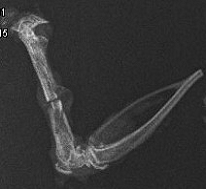

Группа 6

Рентгенологически на 45 сут. эксперимента в 4 случаях отмечается активное формирование костных структур, восстановление костномозгового канала и частично кортикальной пластинки. В 2 случаях слабо прослеживается линия остеотомии. Со стороны периоста и эндоста новообразованная ткань костной плотности соединяла отломки (рис.15).

Рис.15. Типичная рентгенограмма бедренной кости крысы группы 6 через 45 сут. после остеотомии и общего равномерного гамма- облучения 3,0 Гр.

Оптическая плотность зоны регенерата- 0,503 ± 0,015, р < 0,05.

Через 45 сут. после начала эксперимента межотломковая щель заполнена фиброретикулярной тканью с тканевыми кистами, очагами гиалинового хряща, а также с небольшим количеством в основном примитивных и единичных зрелых костных балок, которые определяются также на всем протяжении представленного участка костномозгового канала. Периостально- костная мозоль, состоящая из грубоволокнистой соединительной и хрящевой ткани, и расположенных хаотично зрелых костных балок. Сохранились контуры краев консолидировавшихся отломков. Структура кортикального слоя не до конца соответствует нормальной- имеются расширенные сосудистые каналы (рис.16).